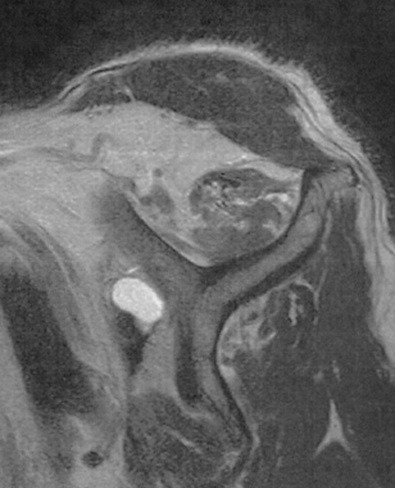

リバース症例の術前MRI所見

広範囲断裂

Goutallier分類Stage3

腱板の断端がみえないほど大きな断裂で脂肪変性もすすんでいます。